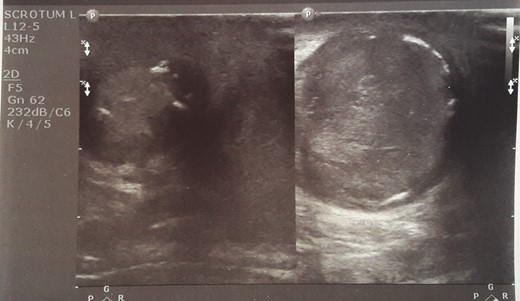

Initial sonographic findings were suggestive of epididymo-orchitis. The testis was well perfused and in normal position (Fig. 1). He was admitted for 3 days to start intravenous anti-inflammatory and antibiotic treatment and discharged under antibiotic treatment. Re-examinations were scheduled to assess treatment. On first reexamination, a week later, edema had subsided and the testis appeared hard, indurated and painless (Fig. 2). Ultrasound was still suggestive of epididymo-orchitis. Nevertheless suspicion for a testicular tumor was raised because of persistence of clinical and sonographic findings. An earlier appointment was scheduled this time. Five days later, at the second reexamination, another ultrasound showed reduced testicular perfusion that reached only the periphery of the testicular parenchyma (Fig. 3). The boy was operated as an emergency. Intraoperatively testis was non-twisted, with normal vas and vessels that ended in a necrotic testicular parenchyma. The testis was dark brown, hard on palpation and no blood came out when incised (Fig. 4). Right orchidectomy was performed. Since the exact cause of testicular necrosis was still unkown at the time of operation a left orchidopexy was performed to protect the only surviving testis from any future risk of torsion. The boy was discharged the next day. Histology showed a case of epididymitis nodosa and ruptured sperm granuloma that caused vascular compression, thrombosis and testicular necrosis (Fig. 5). More specifically, it showed proliferation of small ducts and gland-like structures in the walls of the vas deferens and epididymis in response to fluid and sperm dissection into the interstitium secondary to mechanical obstruction and increased intraluminal pressure. These findings are extremely rare in pediatric patients. The boy had an uneventful postoperative course and was discharged 2 days after surgery able to travel by sea to his home island.

Five days later another ultrasound showed reduced testicular perfusion that reached only the periphery of the testicular parenchyma.